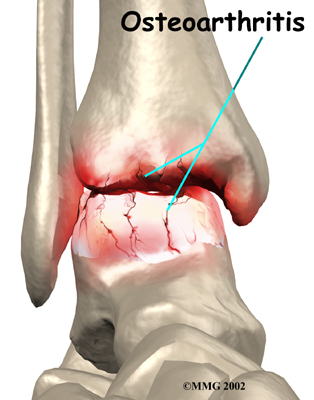

Injury to a joint, such as a bad sprain or fracture, can cause damage to the articular cartilage. The cartilage can be bruised when too much pressure is exerted on it. This damages the cartilage, although if you look at the surface it may not appear to be any different. The injury to the material doesn't show up until months later. Sometimes the cartilage surface is damaged even more severely, and pieces of the cartilage are ripped from the bone. These pieces do not heal back and usually must be removed from the joint surgically. If not, they may float around in the joint, causing the joint to catch and be painful. These fragments of cartilage may also do more damage to the joint surface.

Once this cartilage is ripped away, it does not normally grow back. Unlike bone, holes in the surface are not simply replaced by the cartilage tissue around the hole. Instead the defects are filled with scar tissue. The scar tissue that forms is not nearly as good a material for covering joint surfaces as the cartilage it replaces. It just can't support weight and isn't smooth like true articular cartilage.

Over many years this imbalance in the joint mechanics can lead to damage to the articular surface. Since articular cartilage cannot heal itself very well, the damage adds up. Finally, the joint is no longer able to compensate for the increasing damage, and it begins to hurt. The damage occurs well before the pain begins.